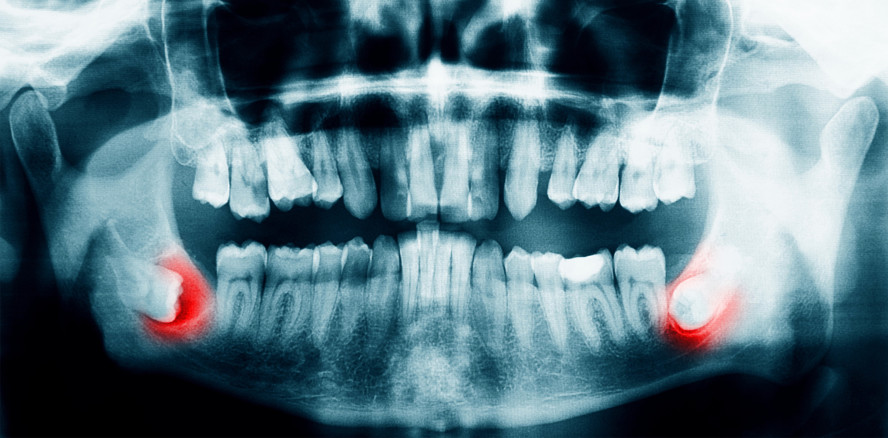

Neue S2k-Leitlinie: „Operative Entfernung von Weisheitszähnen“

Die nach den Regularien der AWMF (Arbeitsgemeinschaft der Wissenschaftlichen Medizinischen Fachgesellschaften) erstellte S2k-Leitlinie zu dem häufigen Eingriff der Weisheitszahnentfernung ist aktualisiert worden. Federführend durch die DGMKG und die DGZMK wurde in Zusammenarbeit mit sieben weiteren beteiligten Fachgesellschaften und Institutionen eine evidenz- und konsensbasierte Grundlage für die häufige und wichtige Therapieentscheidung zwischen dem Belassen und dem Entfernen von Weisheitszähnen erarbeitet. Die Leitlinie und den Methodenreport finden Sie hier.

Foto: gmstockstudio – stock.adobe.com